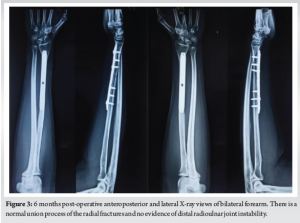

Initial management included bilateral above-elbow splints and intravenous analgesia. Following a detailed discussion with the patient, surgical intervention was planned. Open reduction and internal fixation (ORIF) was performed bilaterally under general anesthesia using a standard Henry’s approach. Both fractures were stabilized using 7-hole limited contact dynamic compression plates (LCDCPs). During surgery, anatomical fracture reduction led to spontaneous DRUJ realignment, confirmed intraoperatively through the piano key test. Fluoroscopy verified proper alignment (Fig. 2). Postoperatively, the patient was immobilized in supination with above-elbow back slabs. Three weeks later, controlled range-of-motion exercises for the wrist, elbow, and shoulder were initiated. Follow-up radiographs showed satisfactory healing. At 1 year, the patient achieved full bony union and functional recovery, scoring 95 on the Mayo wrist score.

This fracture pattern did not fit either category, highlighting the importance of meticulous radiographic evaluation for detecting unusual presentations. In pediatric patients, closed reduction and casting are often sufficient for managing Galeazzi fractures, yielding favorable results. However, in adults, surgical intervention is essential due to the strong deforming forces acting on the radius and DRUJ instability [6]. ORIF using a volar (Henry’s) approach remains the standard technique for treating Galeazzi fractures, allowing direct visualization and precise fracture stabilization [9]. In this case, 7-hole LCDCPs provided stable fixation, enabling controlled early mobilization (Fig. 2). DRUJ integrity was confirmed intraoperatively, with fluoroscopic imaging verifying proper realignment [8]. Post-operative care included immobilization in a long-arm cast for 3 weeks to prevent redislocation, followed by progressive range-of-motion exercises to minimize stiffness and optimize function. Potential complications include non-union, malunion, chronic DRUJ instability, and neuropathy. If inadequately treated, DRUJ injuries can lead to chronic pain and functional impairment, sometimes requiring salvage procedures such as the Sauvé-Kapandji or Darrach operations [10]. This patient achieved an excellent functional outcome without complications. Intraoperative assessment, including the piano key test, confirmed DRUJ stability, negating the need for additional fixation. At the 1-year follow-up, the patient exhibited full range of motion and grip strength (Fig. 3-5).